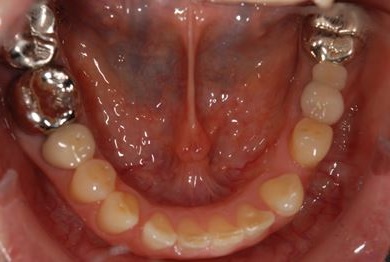

インプラントの症例写真 IMPLANT

インプラント治療

| 性別/年齢 | / 49歳 | ||||||||||||||||||||||||||||||||

| 主訴 | 乳歯がぐらついている。 | ||||||||||||||||||||||||||||||||

| 治療方針 | インプラント治療にて、機能的・審美的回復を行う。 | ||||||||||||||||||||||||||||||||

| 治療内容 | インプラント1本、メタルボンドセラミッククラウン1本 | ||||||||||||||||||||||||||||||||

| 総治療費 | 377,055円 | ||||||||||||||||||||||||||||||||

| 治療期間 | 4ヶ月 |